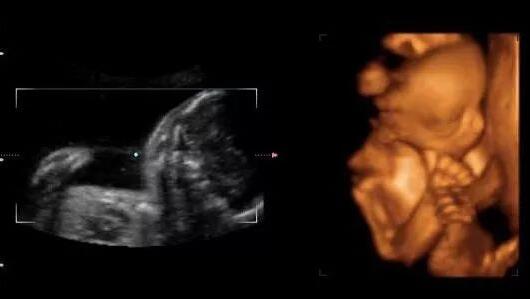

男孩B超图片

一般来说,B超单上的数据有很多,比如双顶径、腹围、股骨长、胎囊、胎心次数等,还可以从B超中观察到胎盘、羊水、脐带、胎儿脊椎等情况。老一辈有些人的说法认为看怀孕40-50天时的B超单,观察孕囊的大小和形状就能看出胎儿的性别,孕囊形状是椭圆或圆形的是女宝宝,长条形的是男宝宝。

当然还有厉害的看单子上面双顶径和股骨长,头大腿短的是男孩,即双顶径-股骨长>2,头和腿相差小的是女孩。